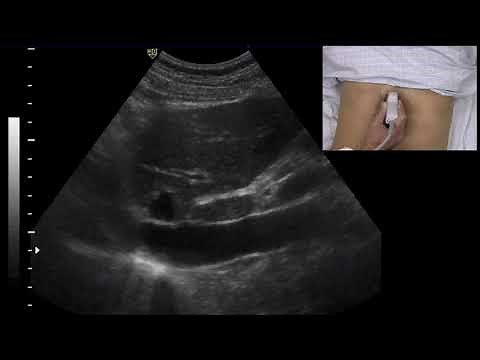

Significant IVC collapse with inspiration | Ahmed Mohsen

Ahmed Mohsen. . Significant IVC collapse with inspiration

Inferior Vena Cava ultrasound- small and collapsing

Ultrasound to measure IVC Collapsibility | IVC collapse demo

ultrasound of total IVC collapse.